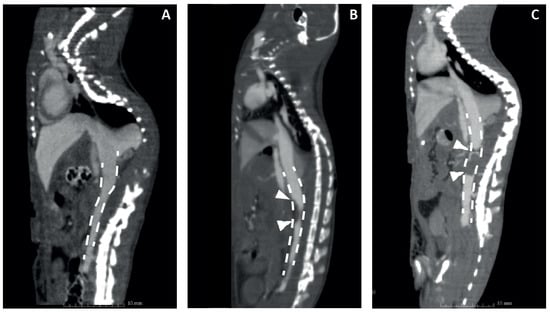

To test the new probe in vivo, two different DVT C57BL/6 mouse models were used. The rapid IVC FeCl 3 model was compared to the IVC stenosis model because the cellular composition and fibrin content are different in the resulting thrombi [,]. Prior to testing the tracer, the models were validated at different time points using CBCT scanning with a single i.v. bolus injection of the contrast agent ExiTron Nano 12000. Representative images are shown in Figure 4, showing an intact V. cava in the mouse receiving sham surgery (A), a lack of contrast on the apical side of the V. cava in the mouse that received FeCl 3 treatment, indicating thrombus formation (B), and a clear negative contrast throughout the V. cava and the location of ligation, indicating an occlusive thrombus in the IVC stenosis model (C).

Figure 4. Evaluation of mouse DVT models by contrast-enhanced CT in a sham-operated mouse (A), 6 h after endothelial damage with FeCl 3 (B) and 24 h after flow restriction by partial ligation (C). The dashed line shows the IVC in the abdominal cavity. Arrowheads point to lack of intravenous contrast, indicating thrombus formation.